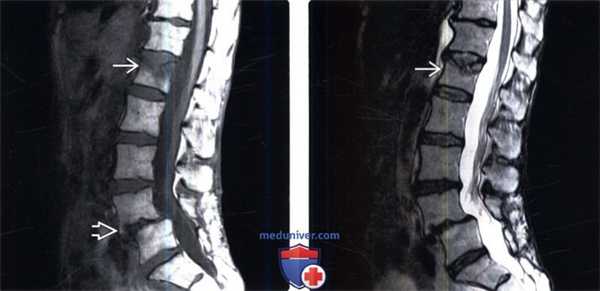

(Слева) Сагиттальный срез, Т1-ВИ: послеоперационные изменения L4-L5 сегмента после ляминэктомии. Выраженные дегенеративные изменения межпозвонкового диска L4-L5 с передним подвывихом L4. Обратите внимание на компрессионный перелом замыкательной пластинки L1.

(Справа) Сагиттальный срез, Т2-ВИ: признаки послеоперационного спондилолистеза, развившегося после ляминэктомии L4-L5, выраженных дегенеративных изменений межпозвонкового диска и жировой перестройки костного мозга в области смежных с этим диском замыкательных пластинок. Обратите внимание на компрессионный перелом L1, который не связан с деформацией нижележащего сегмента.